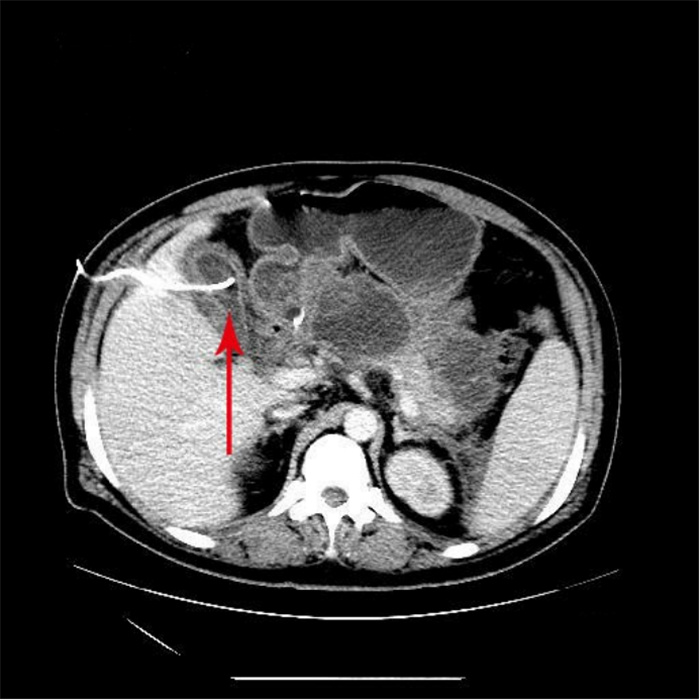

入院第57天,患者再次出现暗红色血便,伴阵发性右上腹痛,无发热、呕血,症状与之前相同。鉴于患者有活动性出血,再次复查胃镜:慢性浅表性胃炎伴糜烂。复查肝功能:γ-GT 844 U/L,TBil 43.6 μmol/L,NCBil 16.6 μmol/L,CBil 27 μmol/L,肝功指标再次回升,γ-GT、CBil明显升高,提示可能出现胆道梗阻。肝胆脾胰腺彩超复查:胆囊肿大、胆囊陈旧性稠厚淤胆(较前无明显变化),胰腺稍大并不均质改变。复查上腹CT:AP复查情况与之前相同,可能有胆囊出血(见图 2)。联合介入放射科行血管造影检查,常规局部麻醉下采用Seldinger技术由右侧股动脉入路,造影发现胆囊动脉分支出血(图 3),超选择胆囊动脉分支用明胶海绵颗粒行栓塞止血(图 4)。同时,行经皮经肝胆囊穿刺置管引流(图 5),病情稳定后带管出院,3月后予以拔除,择期行胆囊切除。

| 胆囊内可见高密度影,A:CT值为62 HU;B:CT值102 HU;C:胰腺假性囊肿引流管 图 2 入院第57天复查腹部CT |

患者病程41 d、57 d查腹部CT分别提示胆囊结石和胆囊内出血的可能性,这是患者入院腹部CT所没有的特征,检测胆囊内病灶CT值为62~102 HU。多学科会诊中大部分专家意见认为胆囊出血临床极罕见,胆囊内病灶并不考虑出血,仍考虑结石可能性大。因患者首次便血后给予对症治疗后便血症状停止,故没有选择血管造影进一步检查明确病因。